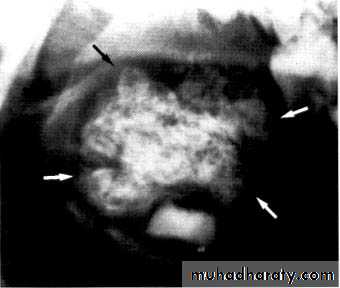

Osteosarcoma

Rare, rapidly destructive malignant tumor of bone. The cause of osteosarcoma is unknown, but genetic mutation and viral causes have been suggested. It is also known to occur in association with Paget’s disease and fibrous dysplasia after therapeutic irradiation.

Early features:

Non-specific, poorly defined radiolucent area around one or more teeth.

Widening of the periodontal ligament space.

Later features:

• Osteolytic lesion:— Monolocular, ragged area of radiolucency — Poorly defined, moth-eaten outline.

— So-called spiking resorption and/or loosening of associated teeth.

• Osteosclerotic and mixed lesions:

— Poorly defined radiolucent area

— Variable internal radiopacity with obliteration of the normal trabecular pattern

— Perforation and expansion of the cortical margins by stretching the periosteum, producing the classical, but rare sun ray or sunburst appearance

— Spiking resorption and/or loosening of associated teeth

— Distortion of the alveolar ridge.